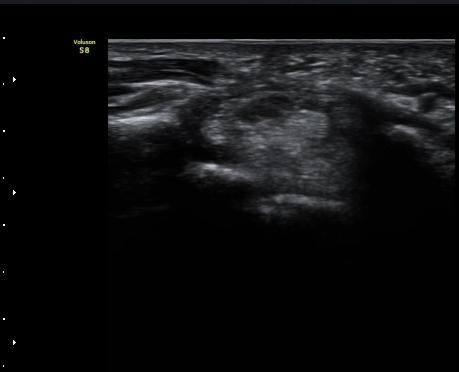

¼Õ¸ñ(lunate ±âÁØ)°ú ¼ö±Ù°ü ±ÙÀ§ºÎ(scaphoid ±âÁØ) Á¤Á߽Űæ Ⱦ´Ü¸é°Ë»ç¿¡¼­ Á¤»óÀûÀÎ

¸ð¾çÀ¸·Î °üÂûµÈ´Ù(±×¸² 1, 2).